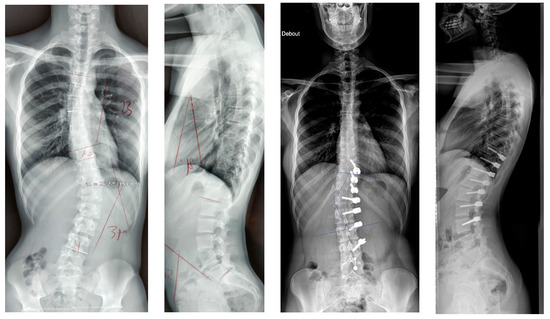

2.2. Surgical Technique

3. Results

| Major curve | 43.9° (9.2) | 20.3° (16.2) | 13.2° (28.2) |

| Secondary curve | 29.1° (12.6) | 21.9° (11.2) | 19.9° (13.9) |

| Kyphosis (T4T12) | 23.2° (7.8) | 25.1° (9.5) | 26.9° (12.6) |

| Lordosis (L1L5) | 41.7° (7.8) | 42.4° (10.1) | 42.8° (7.5) |